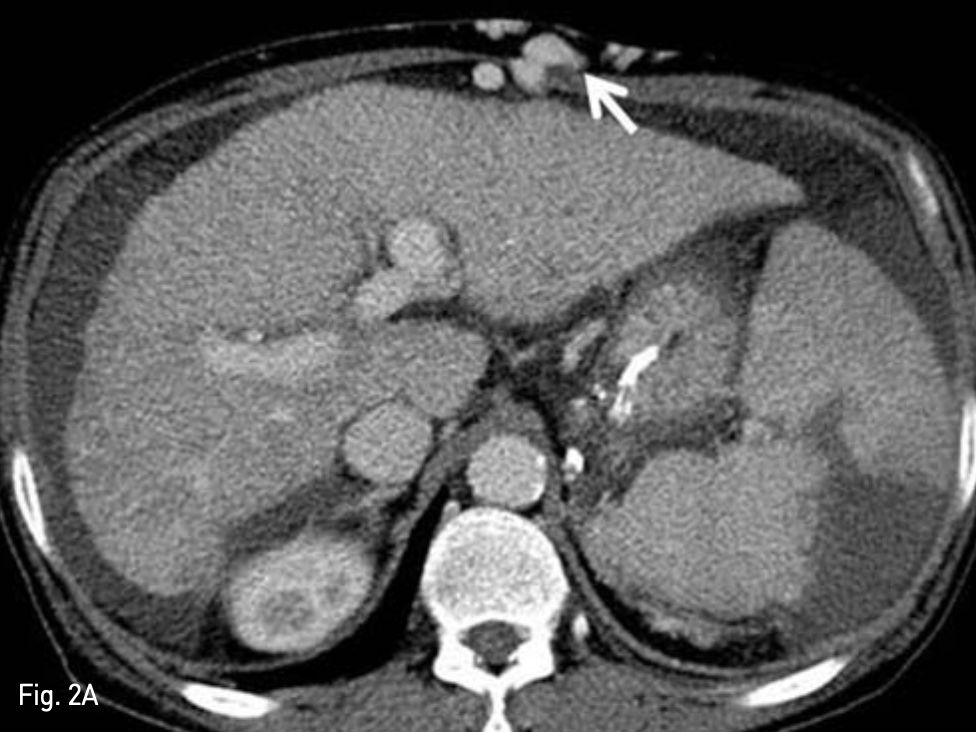

Fig. 2

Liver dynamic CT for preprocedural evaluation

A. Venous phase CT image revealed dilated recan alized paraumbilical vein in abdominal wall (arrow)

B. This recan alized paraumbilical vein drains left portal vein (arrow).